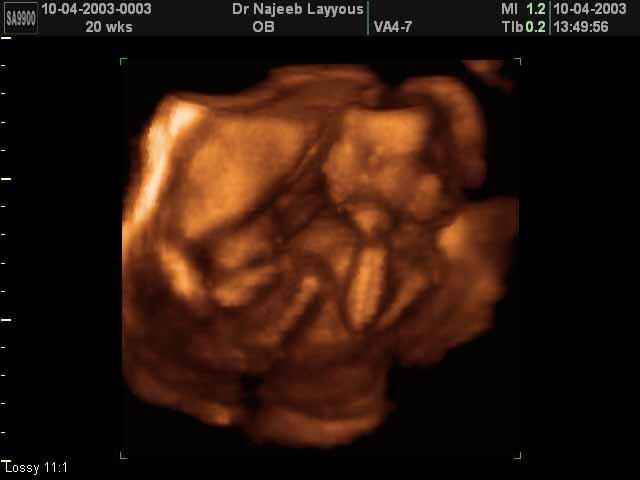

- Fetal Behavior Ultrasound Photos

- Second Trimester Ultrasound Photos

3D Second Trimester Ultrasound Scan Photos-second part of pregnancy | Dr N Layyous